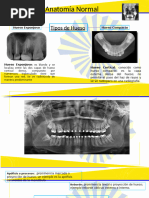

DIAGNÓSTICOS QUIRÚRGICOS BUCALES:

- O.D 18 disto angular, posición B, relacionado con seno maxilar.

- O.D 28 vertical, posición A, relacionado con seno maxilar.

- O.D 3.8 vertical, clase I, posición A.

- O.D 48 vertical, clase I, posición A